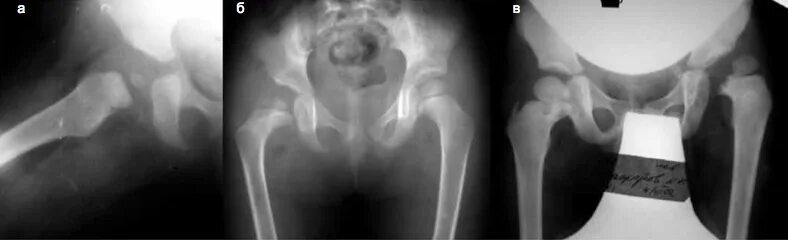

Патологическим называется вывих